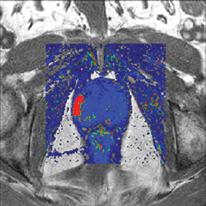

Radiation therapy is an important clinical option for the alleviation of pain and suffering for cancer patients and is used for palliative treatments to prevent pathologic bone fractures or tumor-induced obstructions, bleeding and pain that is resistant to other treatments. However, standard palliative radiation therapy treatment techniques often offer poor conformality and expose large volumes of normal tissues to radiation-induced toxicities, causing significant side effects for an already ill patient with a limited life expectancy.

Perhaps one of the most frightening experiences a patient can have is an inconclusive cancer test, where the biopsy is negative, but several other signs point to the possibility that the disease may be present. For some prostate cancer patients, this frightening scenario is a reality.